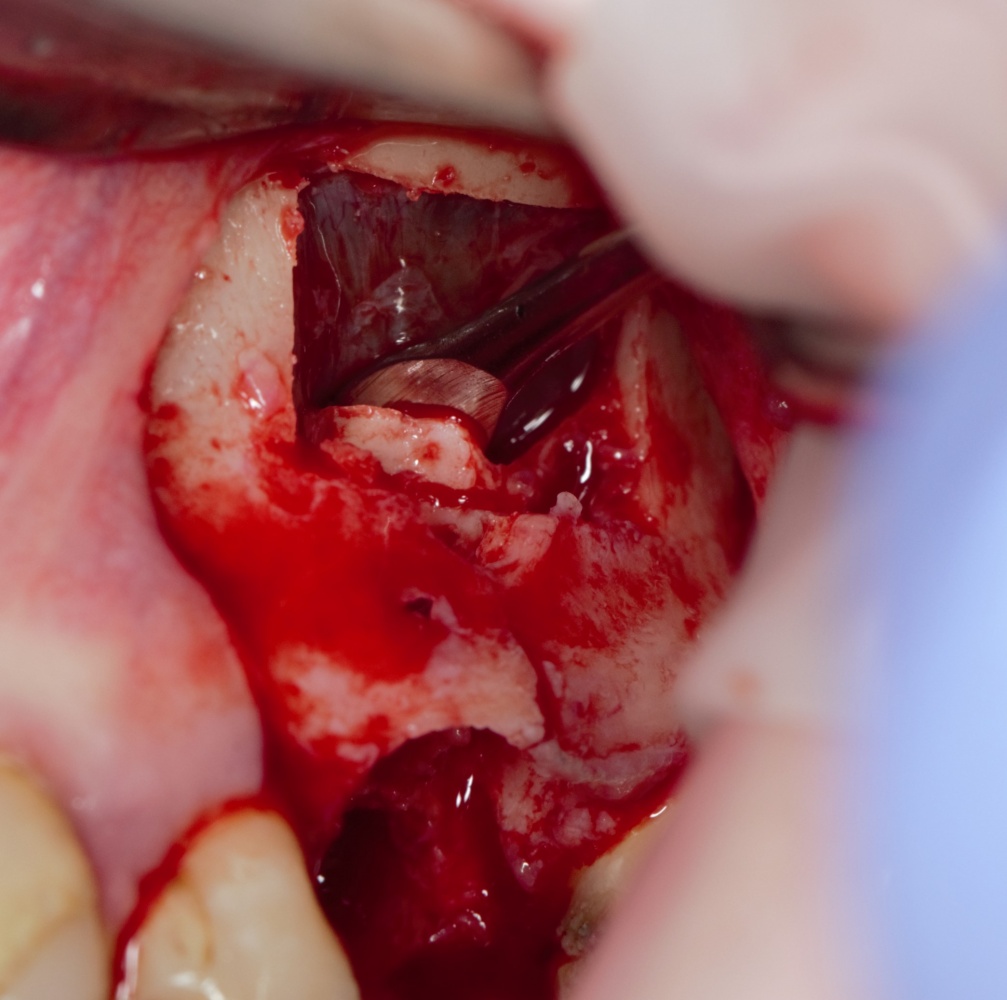

Простой синуслифтинг. Часть I.